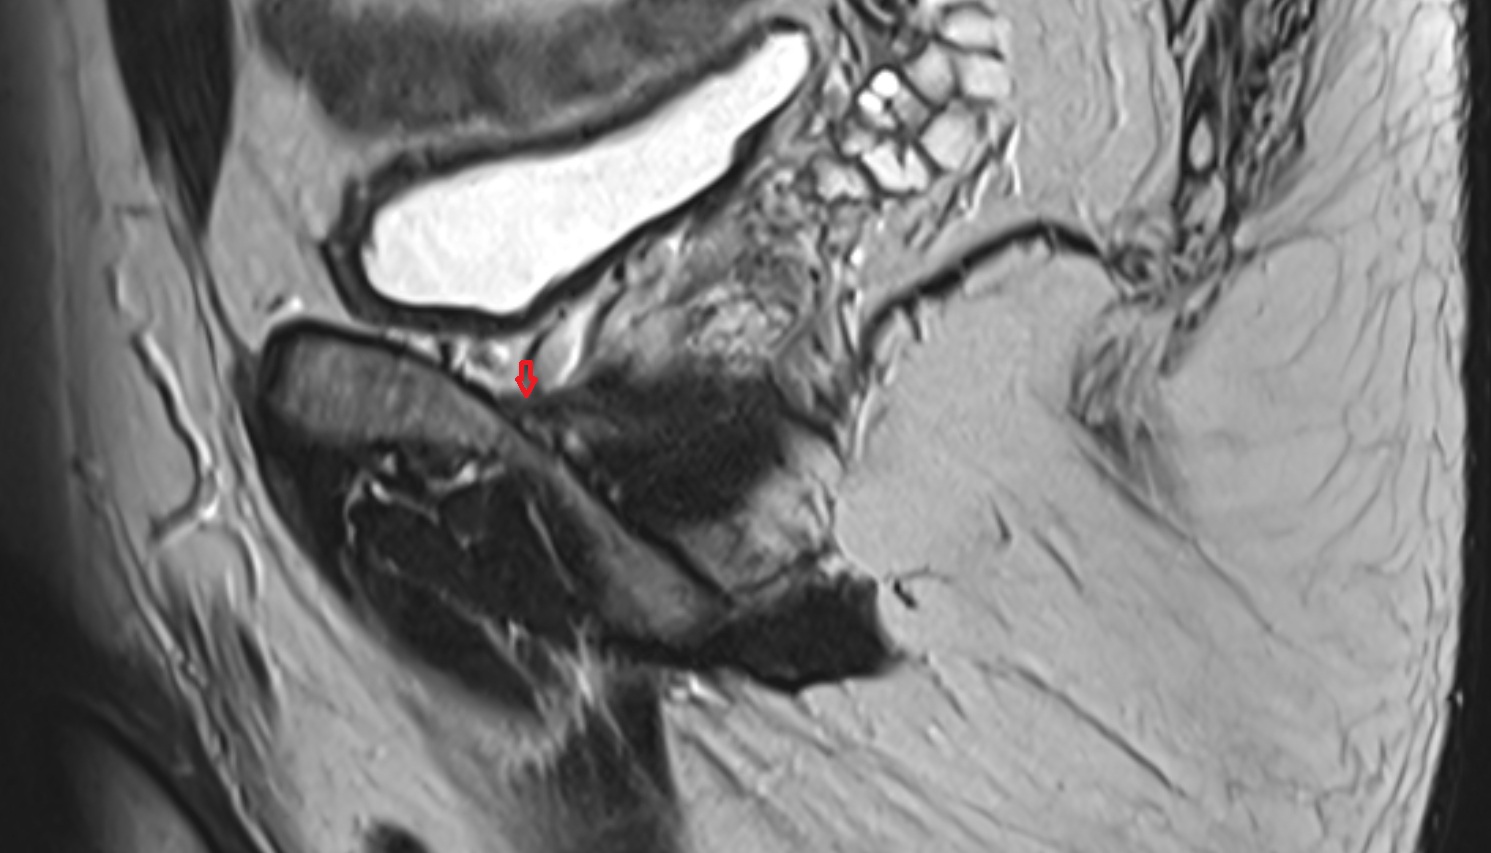

- Prostatic urethra

- Membranous urethra

- Penile urethra

- Seminal vesicle

- Ejaculatory duct